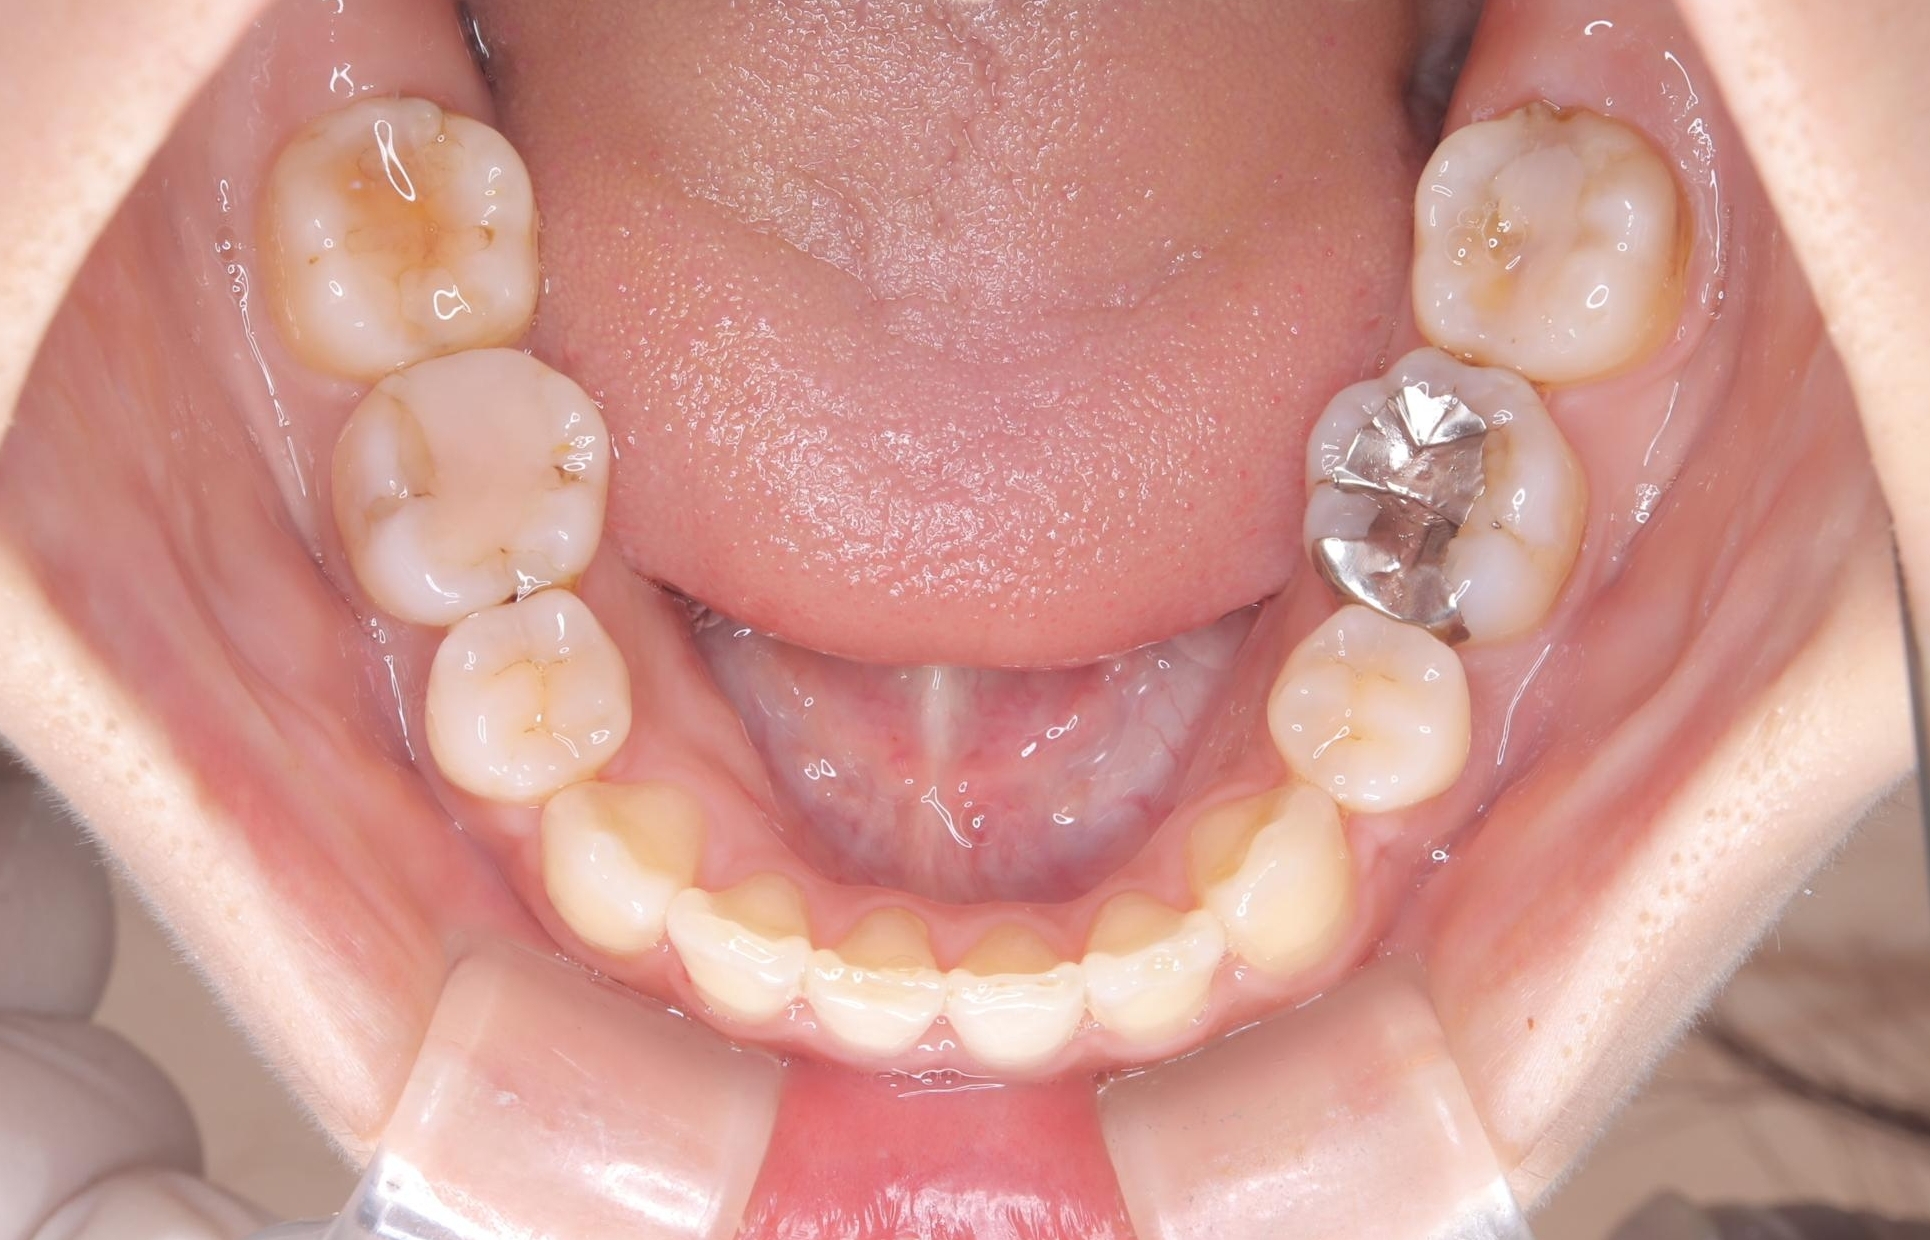

- 主訴:口元を下げて前突感を無くしたい、下の歯の凹凸も無くしたい

右側第二小臼歯、左側第一小臼歯、下顎両側第一大臼歯を抜歯しワイヤ-矯正を行いました。

骨格的顎の変位を認めたため、顔貌に対しピッタリ上下の歯の正中を合わせることは難しいと説明し、上下左右計4本小臼歯を抜歯しワイヤー矯正治療を行いました。